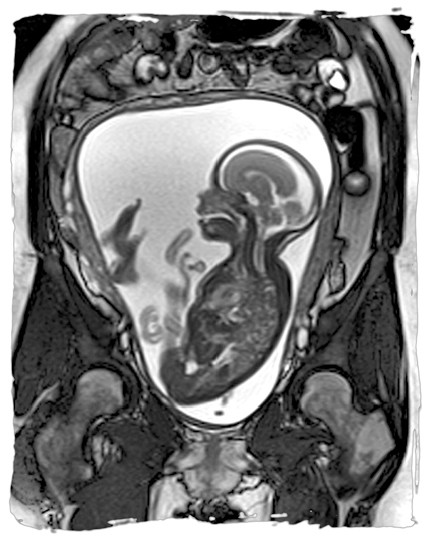

دلایل انجام ام آر آی جنین در بارداری

تصویربرداری

1404/11/29

ام آر آی جنین ، تصویربرداری است که به کمک آن می توان اطلاعات دقیقی درباره وضعیت جنین و رحم مادر به دست آورد. این روش به...

نوبت دهی ام آر آی جفت در بارداری

ام آر آی جفت روش تصویربرداری پزشکی است که با استفاده از میدان های مغناطیسی و امواج رادیویی، تصاویر دقیقی از ساختار داخلی...